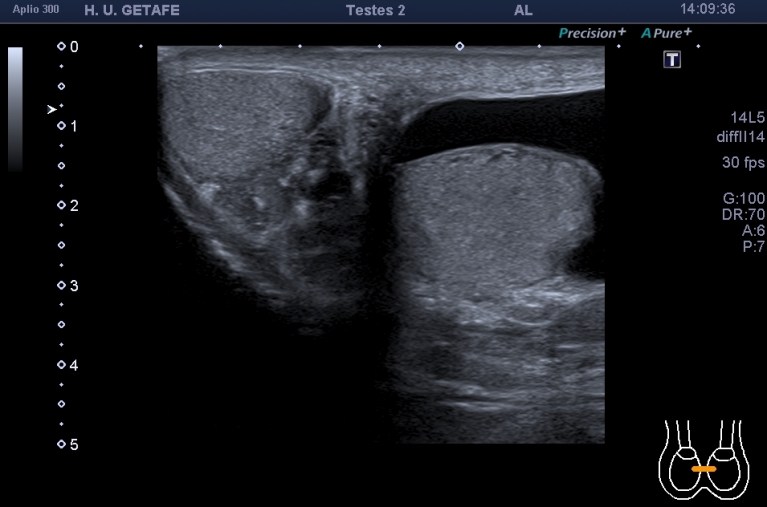

Se pide ecografía testicular por sospecha de hidrocele secundario a afectación del cordón por el tumor intraabdominal, a filiar. No se pudo poner contraste en el CT.

En la exploración observamos hidrocele unilateral izquierdo. En el canal inguinal puedes ver una estructura similar a una hernia inguinal, que con la maniobra de valsalva permanece inmóvil y por tanto no compatible con hernia a ese nivel de comportamiento normal y que podría estar provocando el hidrocele anteriormente referido.